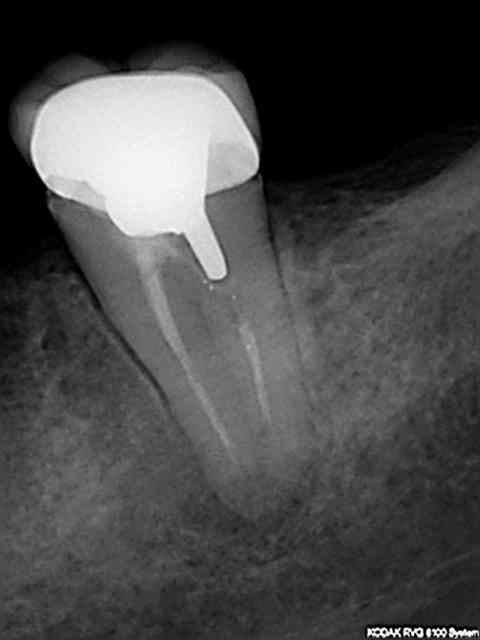

J'utilise le système heroshaper+digue+hypo+condensation

Mac Spadden(thermomécanique)

J'ai posté des radios biopulpectomies et retraitements

canalaires précédemment.

L'obturation 3D est indispensable pour un traitement hermétique.Mon associé utilise le système protaper et

effectivement cela élargit plus.Sur ces 7 dernières années

j'obtiens de bons résultats;mon avis le système heroshaper

casse moins mais n'hésite pas à jeter un heroshaper

même si non déspiralé ;si il a travaillé un peu en force

ou si la morphologie canalaire est un peu compliquée ou courbe;on fait un peu un usage unique pour éviter tout

problème plus tard!(quelque soit le système)on récapitule

avec un instrument à mains;pour une bonne herméticité

le système Mac spadden est le plus efficace ,utlisé par des endos exclusifs,et le moins cher (un cone de gutta est suffisant)Ma séquence classique instrument à main N10

héroshaper N20 6%/4% N25 4% N30 4% MAC SPADDEN un cone de gutta/ciment sealite régular

J'ai reposté quelques radios de biopulpectomies

RTE dans un précédent post...